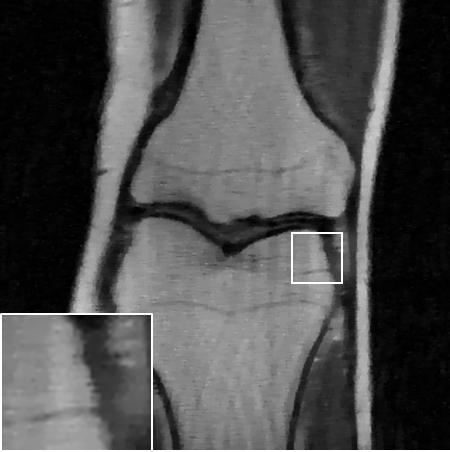

Table LABEL:tab:quant_results summarizes the results for the various experimental settings, comparing the performance of the above-mentioned benchmarks to ours. When compared to TV [6], our method achives an improvement of dB-dB in the peak-signal-to-noise ratio (PSNR). Similar results are observed for the structural-similarity measure (SSIM, about points improvement). As expected, the supervised model outperforms the proposed SSL method. However, it seems that at least for the lower distortion rates, this gap is surprisingly small. A visual inspection of the results over one slice is provided in Fig. 3. As can be observed in the zoomed-in region, our method manages to restore finer details better than the TV-based method, and even approaches the restoration levels of the supervised model in the lower distortion rates. As evident both quantitatively and visually, the TV-based method completely fails on the dealiasing task, whereas our SSL method seems to significantly alleviate the reconstruction artifacts.